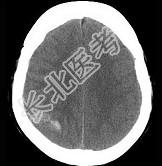

- 单项选择题男,37岁, 头痛、头晕1年余,加重3天, CT检查如图所示,最可能的诊断是 ( )

A、脑血管畸形并出血

B、转移瘤并出血

C、颅内动脉瘤

D、脑出血

E、脑膜瘤并出血